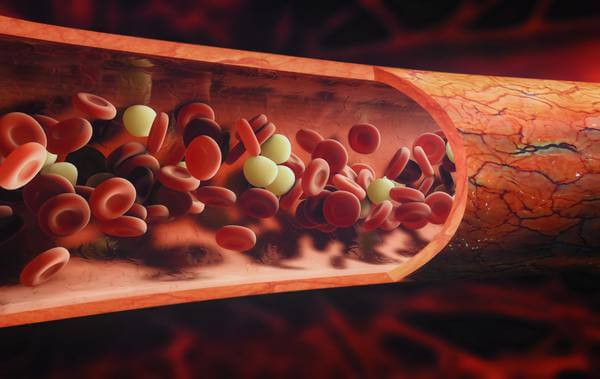

- Cavidade interna grande, o que reduz a fricção quando o sangue é transportado;

- Sangue sendo movido em baixa pressão;